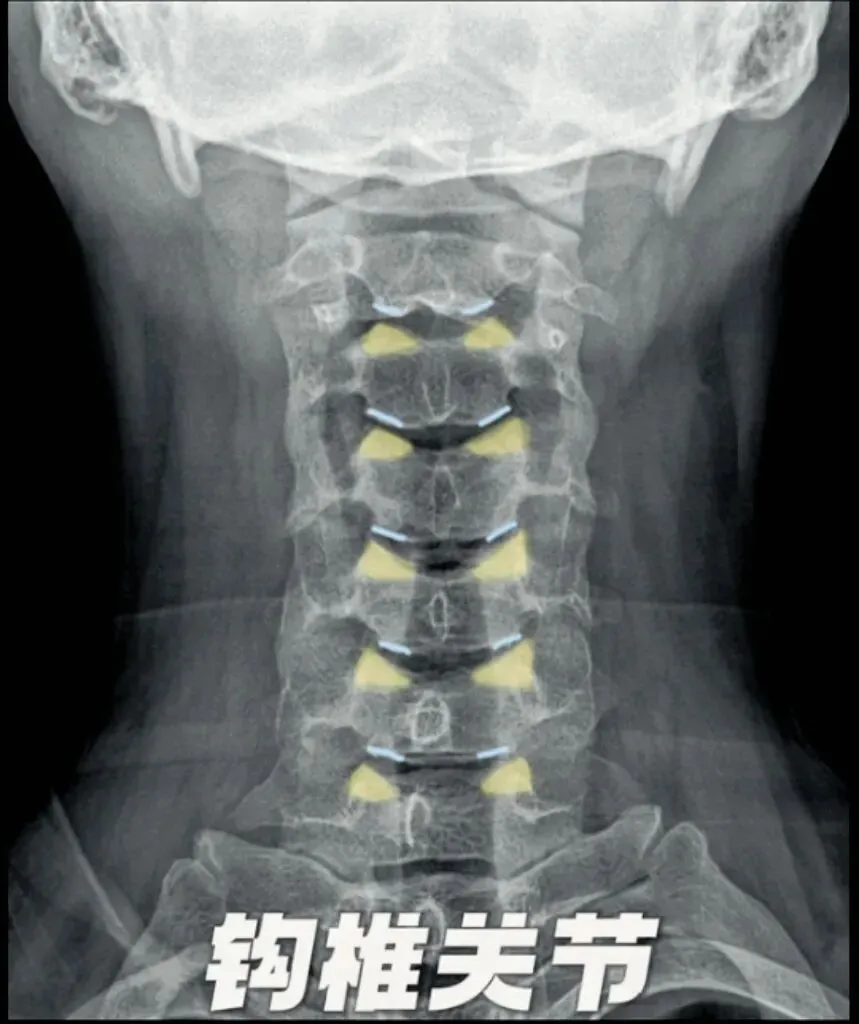

三钩突,颈椎钩突是指颈椎椎体侧方的骨性突起,位于第3至7颈椎椎体上面侧缘,

与上位椎体的下面外侧缘共同构成钩椎关节,

可限制椎间盘向侧方突出,维持颈椎的活动度和稳定性。在斜位片中可更清晰的显示钩椎关节的间隙和钩突与周围结构的关系。

因为钩突离椎间孔非常近,所以当钩突退变发生增生肥大、变尖形成骨刺等变化时会引起相邻椎间孔、横突孔、椎管的狭窄,使得颈神经根、椎动脉和脊髓受压,引起相应的颈椎病症状和体征。